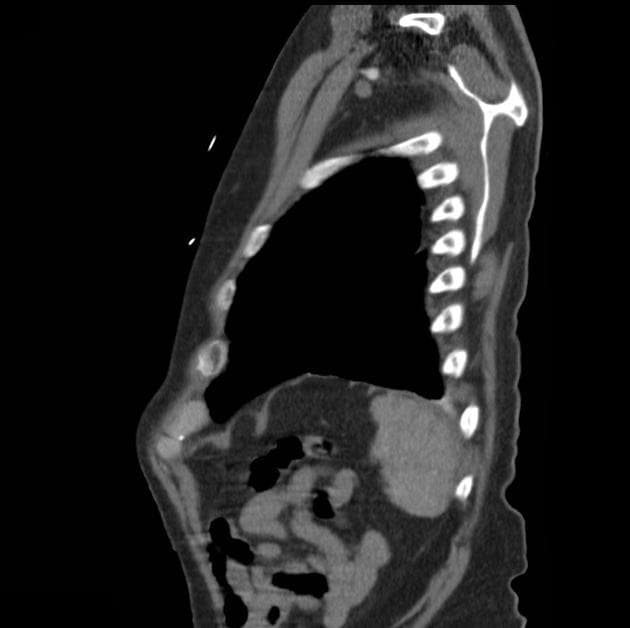

- Không thấy hình ảnh (no evidence of) vỡ thất, nhưng hình ảnh động (cine images) cho thấy thành trước giữa thất trái bị rối loạn vận động (dyskinetic), phồng ra ngoài trong thì tâm thu.

- Trên hình STIR, đoạn cơ tim tổn thương tăng tín hiệu (hyperintense), phù hợp với phù (edema).

- Vị trí tổn thương là bất thường, vì thường thì các đoạn đỉnh (apical segments) bị ảnh hưởng trong bệnh lý này. Tuy nhiên, ba kiểu hình ảnh khác biệt đã được ghi nhận: hai thất (biventricular), giữa thất (mid-ventricular – như trường hợp này), và đoạn đáy (basal).

- Trên cộng hưởng từ (MRI), các phát hiện điển hình gồm phù cơ tim (myocardial edema) và không có thiếu máu cục bộ (ischemia) hay xơ hóa (fibrosis), điều này được chứng minh bằng việc không tăng quang ở thì muộn sau tiêm gadolinium (lack of enhancement at late gadolinium imaging).

Bệnh cơ tim Takotsubo, còn gọi là bệnh cơ tim do stress, đặc trưng bởi rối loạn chức năng thất trái tạm thời do stress về mặt cảm xúc hoặc thể chất, thường gặp ở phụ nữ sau mãn kinh. Mặc dù thể 'phình đỉnh' cổ điển là phổ biến nhất, các thể bất thường như thể giữa thất, thể đáy và thể hai thất ngày càng được nhận biết rõ. Trường hợp này biểu hiện thể giữa thất với rối loạn vận động của thành trước giữa và phù cơ tim trên cộng hưởng từ, nhưng không có dấu hiệu nhồi máu hay xơ hóa. Việc không thấy tăng quang muộn là điểm phân biệt quan trọng với tổn thương do thiếu máu. Diễn tiến lâm sàng với cải thiện tự phát trong vài tuần khẳng định chẩn đoán. Nhận biết các biểu hiện bất thường này là rất quan trọng để tránh chẩn đoán nhầm thành hội chứng vành cấp.